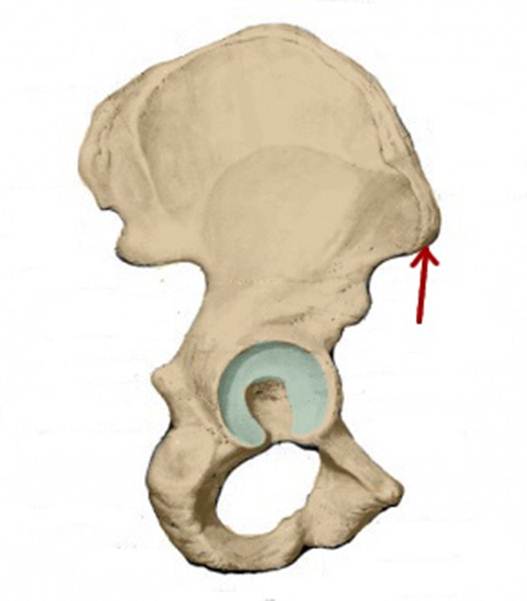

I:

S: Стрелка указывает на os pubis (латинский язык).

I:

S: Стрелка указывает на os ilium (латинский язык).

I:

S: Стрелка указывает на os ischii (латинский язык).

I:

S: Стрелка указывает на ramus superior ossis pubis

I:

S: Стрелка указывает на ramus inferior ossis pubis

I:

S: Стрелка указывает на ramus ossis ischii

S: Стрелка указывает на foramen obturatum (латинский язык).

S: Стрелка указывает на facies lunata (латинский язык).

S: Стрелка указывает на spina iliaca anterior inferior

S: Стрелка указывает на incisura acetabuli

S: Стрелка указывает на spina iliaca anterior superior